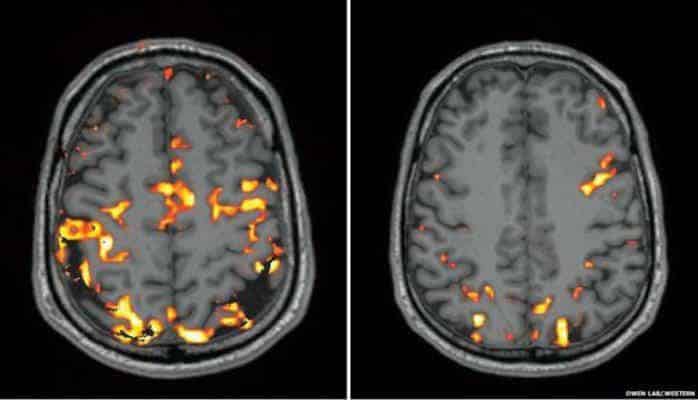

Şəkildə beyinin tam yuxu aldıqdan və solda yuxusuz gecədən sonrakı fəaliyyət görünüşü

MRT beyinə axan qanı müəyyənləşdirə bilir: qrafikdə narıncı ləkələr kimi görünən hissələrdə qan daha güclü hərəkət edir.

Hər iki skan arasındakı fərq dərhal gözə çarpırdı: yuxusuz gecədən sonra, beynimin aktivliyi adekvat deyildi, yəni, beynimdə daha az proses baş verirdi.

"Beyinin qərar, yaddaş və məsələlərin həlli üçün cavabdeh hissələri kimi bilinən alın və pariyetal hissələrində azalma müşahidə olunur," professor Owen izah edir.